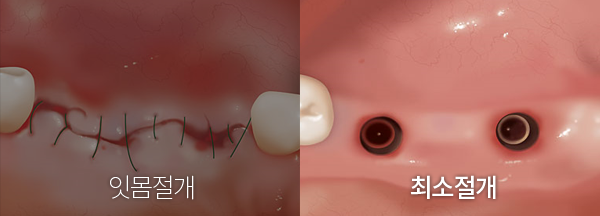

ÄÄÇ»ÅÍ ºÐ¼®À» Ȱ¿ëÇÑ ÀÓÇöõÆ®´Â ½Ã¼ú ½Ã Ä®·Î ÀÕ¸öÀ» Àý°³ÇÏ´Â ¹æ¹ýÀÌ ¾Æ´Ñ

ÀÓÇöõÆ® ½Ä¸³ ºÎºÐ¸¸ ÀÛÀº ȨÀ¸·Î ±¸¸ÛÀ» ¶Õ¾î ½Ã¼úÇÏ´Â ¹æ¹ýÀ¸·Î

¼ö¼ú ÈÄ ÅëÁõÀ̳ª º×±â, ÃâÇ÷ÀÌ °ÅÀÇ ¾ø¾î ȯÀÚ°¡ ÆíÇÑ ½Ã¼ú¹æ¹ýÀÔ´Ï´Ù.

ÃÖ¼ÒÀý°³½Ã¼ú·Î ÅëÁõÀÌ Àû°í ȸº¹ÀÌ ºü¸¨´Ï´Ù.

ÀÏ¹Ý ÀÓÇöõÆ® ½Ã¼úÀº, ÀÕ¸öÀ» Àý°³ÇϹǷΠ¸¹Àº ÃâÇ÷°ú º×±â°¡ µ¿¹ÝµÇ¸ç ȸº¹±â°£ÀÌ ±æ¾îÁö°í ¹«Àý°³ ½Ã¼ú¿¡ ºñÇØ ¿°Áõ ¹× °¨¿°ÀÇ À§ÇèÀÌ ³ô½À´Ï´Ù. ÄÄÇ»ÅÍ ºÐ¼®À» Ȱ¿ëÇÑ ÀÓÇöõÆ®´Â ÃÖ¼ÒÀý°³·Î ÀÛÀº ȨÀ» ÅëÇØ ÀÓÇöõÆ®¸¦ ½Ä¸³ÇϹǷΠº×±â¿Í ÃâÇ÷ÀÌ °ÅÀÇ ¾ø½À´Ï´Ù. ¿°Áõ ¹× °¨¿° À§ÇèÀÌ ÁÙ¾îµé¾î ºü¸¥ ȸº¹ÀÌ °¡´ÉÇÕ´Ï´Ù.